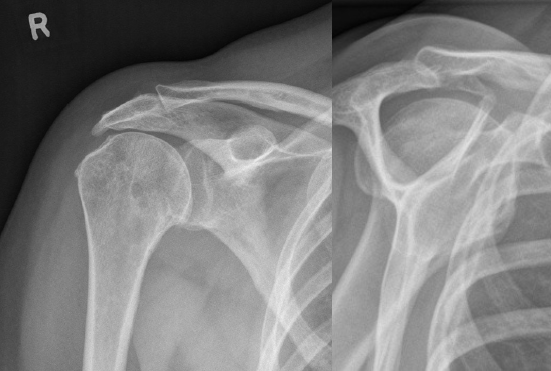

Proyecciones de Rx para ver el desgarro de manguito rotador

• AP

• Oblicua en Y

Datos en Rx que sugieren pinzamiento (lesión)

• Osteofitos acromioclaviculares

• Disminución del espacio subacromial (< 7 mm)

• Irregularidad de cabeza humeral